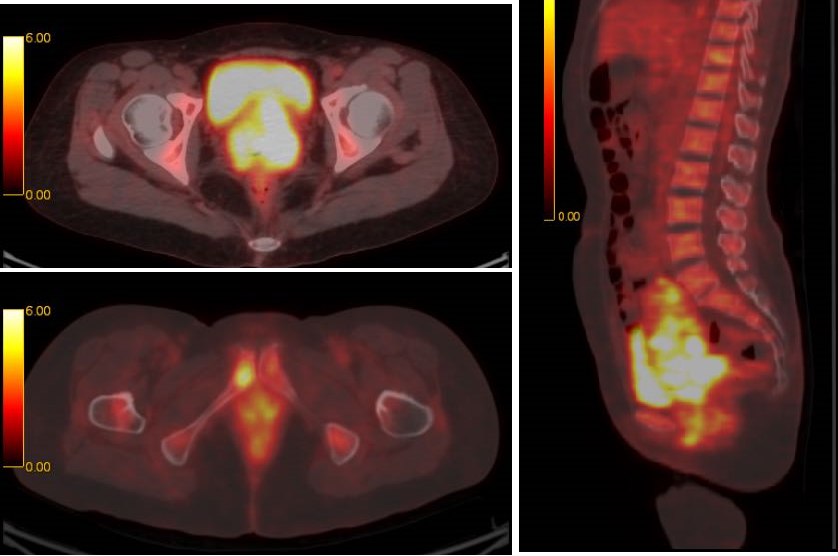

PET-CT检查:

1、宫颈见软组织块,FDG代谢增高,考虑宫颈癌可能大,伴阴道及子宫下段受侵犯可能,直肠受侵犯待排。

2、右侧趾骨下支近趾骨联合见骨质破坏,FDG代谢增高,考虑骨转移可能。

3、胸膜后,两侧髂血管周围,两侧盆壁,见多发大小不等淋巴结,FDG代谢增高,考虑淋巴结转移可能大。

11

图5. PET-CT结果:多处见转移可能